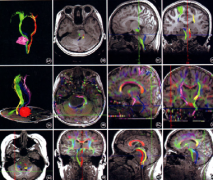

• 腦干膠質(zhì)瘤影像學(xué)、病理學(xué)、分子學(xué)分型

腦干膠質(zhì)瘤影像學(xué)、病理學(xué)、分子學(xué)分型

2020-07-28 16:36:24

摘要:詳細(xì)介紹腦干膠質(zhì)瘤影像學(xué)、病理學(xué)、分子學(xué)分型 是什么決定著腦干膠質(zhì)瘤手術(shù)、放化療方案制定及預(yù)后評估,跟著專家咨詢共識一文深入了解。...